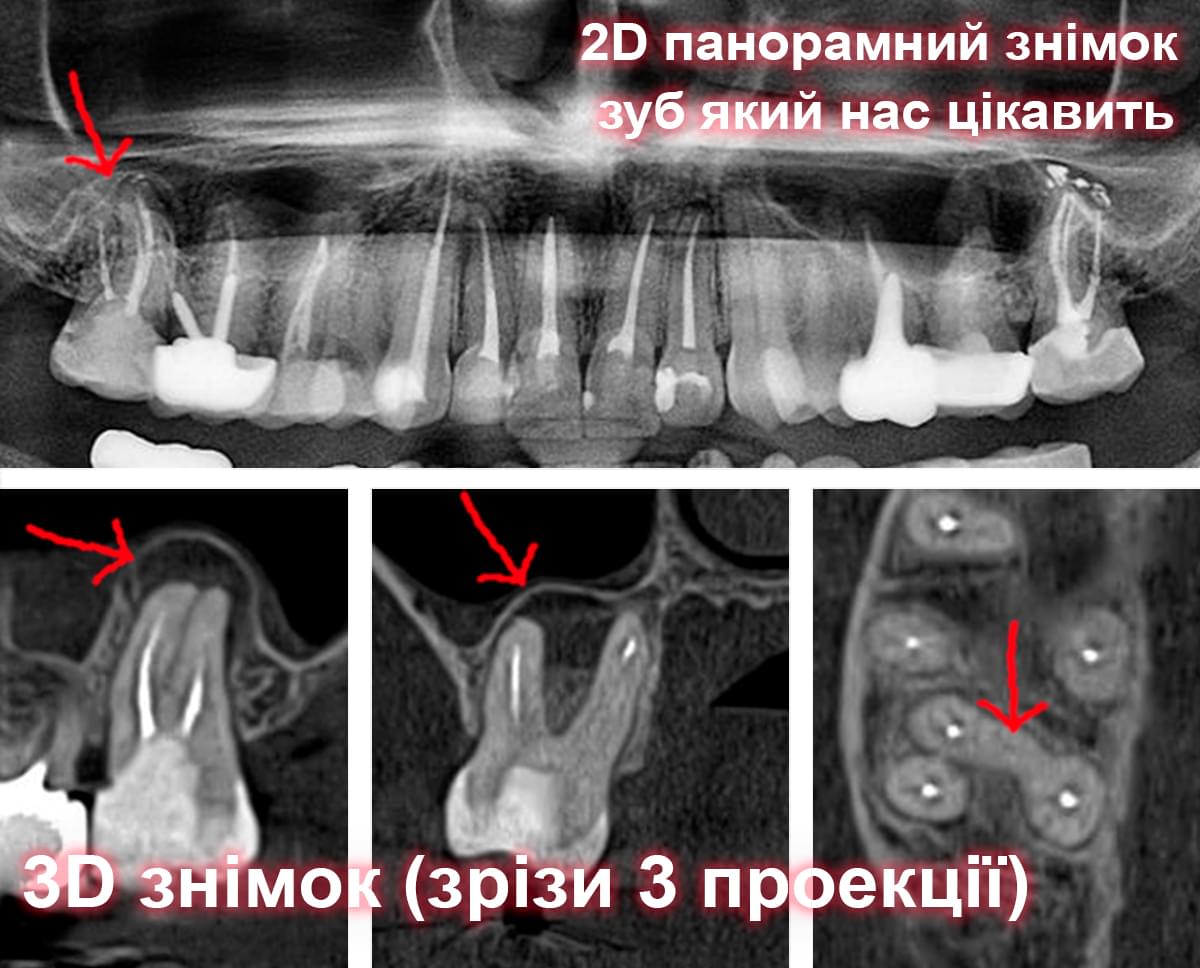

Головний недолік 2D-рентгену — це площинне зображення. Зуби, корені, щільна кістка та гайморові пазухи накладаються один на одного, створюючи «візуальний шум».

Візуальне порівняння (Кейс одного пацієнта)

Зуб — це не просто монолітний об'єкт, а складна система мікроканалів. На плоскому 2D-знімку вони часто перекривають один одного, створюючи ілюзію простої анатомії.

Непомічений канал — це джерело майбутньої інфекції та причина «загадкового» болю після лікування. Завдяки високій роздільній здатності обладнання MyRay, лікар бачить кожен мікронний канал ще до того, як візьме до рук інструмент.